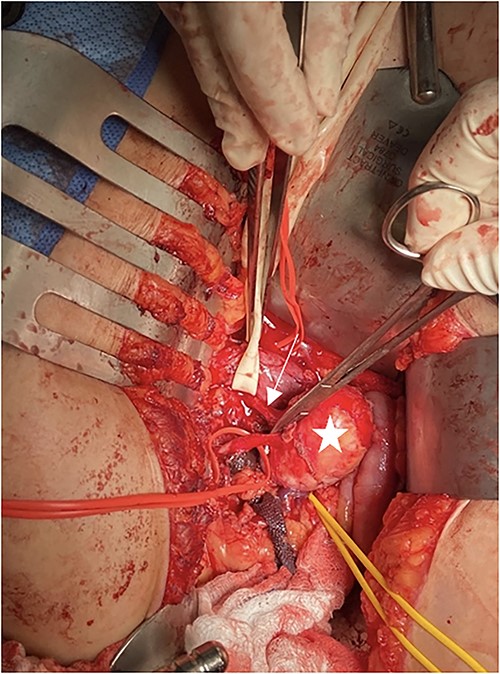

The patient was seen by a rheumatologist for assessment of a genetic cause of a solitary renal aneurysm such as fibromuscular dysplasia or vascular Ehlers Danlos. However, given her clinical presentation and imaging findings, this was not believed to be the case. During this initial consultation, the patient’s physical examination revealed blood pressure of 179/87 in the right arm and 173/124 in the left arm, reflecting uncontrolled hypertension. At the time of consultation, the patient was on Ramipril 5 mg PO once daily and was subsequently increased to Ramipril 5 mg PO BID afterwards. The patient was taken to the operating room for an open repair and resection of the right renal aneurysm with patch angioplasty. In the operating room, a laparotomy was performed, and the saccular aneurysm wall was resected and repaired with a bovine pericardial patch (Fig. 2). During the repair, an 8 mm Argyle shunt was inserted easily to maintain renal perfusion and prevent warm ischemia time. There was between 5 and 10 min of right renal artery ischemia during the procedure. The patch was closed and there were good Doppler signals distally. At the end of the procedure, the patient was making urine. There were no intraoperative complications.

Intraoperative picture of RAA. Penrose is around the inferior vena cava, arrow shows the renal artery, star is on the RAA, and yellow vessel loop is around the renal vein.